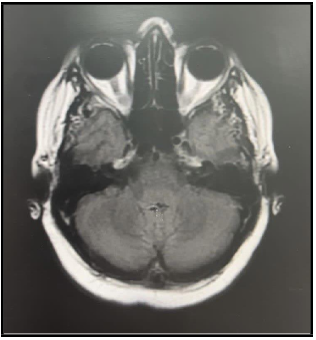

Glomus Tympanicum: A Case Report